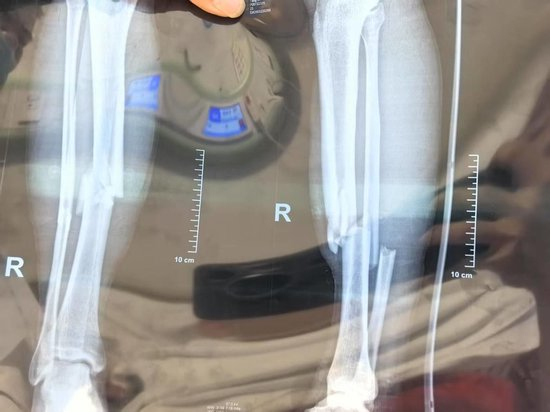

▲小杨医学影像显示为胫腓骨骨折 受访者供图

受伤后,小杨被场边的救护车送往医院,比赛恢复后继续进行。最终,榕江队以2:1战胜对手,获得这项赛事的总冠军。而在医院的小杨,被确定为胫腓骨骨折。